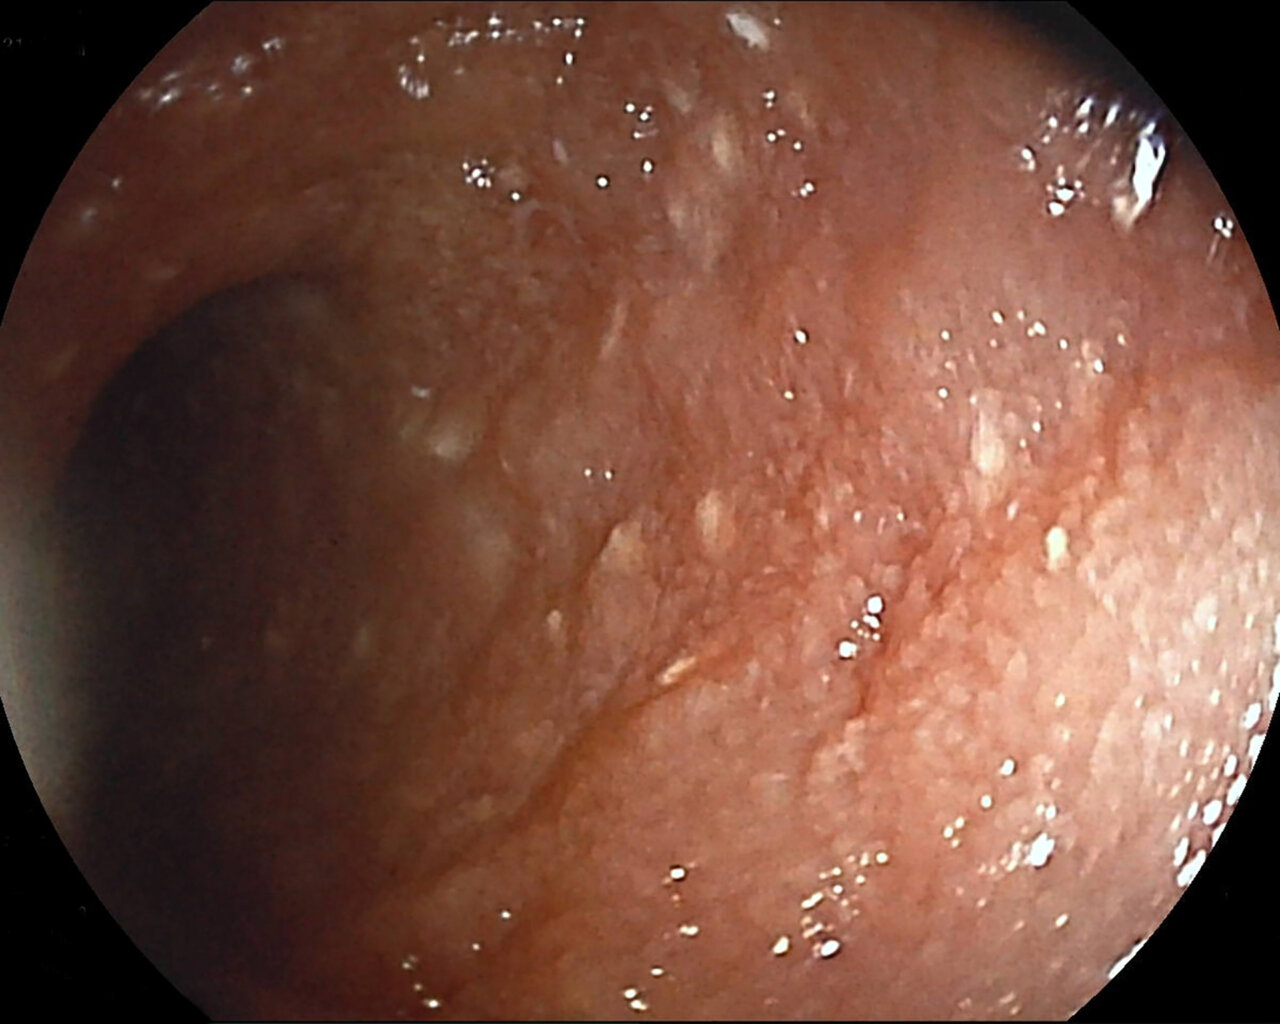

La biopsia y la histopatología de la pared intestinal son necesarias para un diagnóstico definitivo. Se ha puesto en duda en diversas ocasiones la validez de la biopsia endoscópica para la detección de linfangiectasia intestinal, pero un estudio más reciente mostró resultados similares a los que previamente se habían descrito en biopsias de espesor completo23. Teniendo en cuenta esto, en la mayoría de los casos la biopsia endoscópica será la primera opción (salvo presencia de lesiones focales), ya que se trata de animales que presentan alteraciones que podrían complicar la cirugía y posterior cicatrización, como el riesgo de trombosis, la hipoalbuminemia o el déficit de vitamina D. Además, la apariencia macroscópica también nos aporta información y puede guiar la toma de muestras (imagen 3).

Imagen 3. A y B) Imagen endoscópica de un paciente con linfangiectasia. Los puntos blancos que se aprecian en la mucosa duodenal se corresponden con conductos linfáticos dilatados con acúmulo de linfa en su interior. La biopsia confirmó la presencia de linfangiectasia intestinal, probablemente asociada a enteritis linfoplasmocitaria.